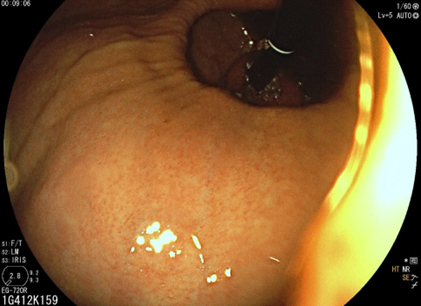

Depuis un an, elle rapporte des crampes d’estomac, notamment après des repas copieux, évoluant par périodes, ainsi qu’un pyrosis nocturne plusieurs fois par semaine. Elle a remarqué dernièrement une gêne thoracique lorsqu’elle boit de l’alcool et lors de ses séances de sport. Il n’y a pas de troubles du transit.

Le pyrosis et le syndrome postural sont des signes typiques de RGO.